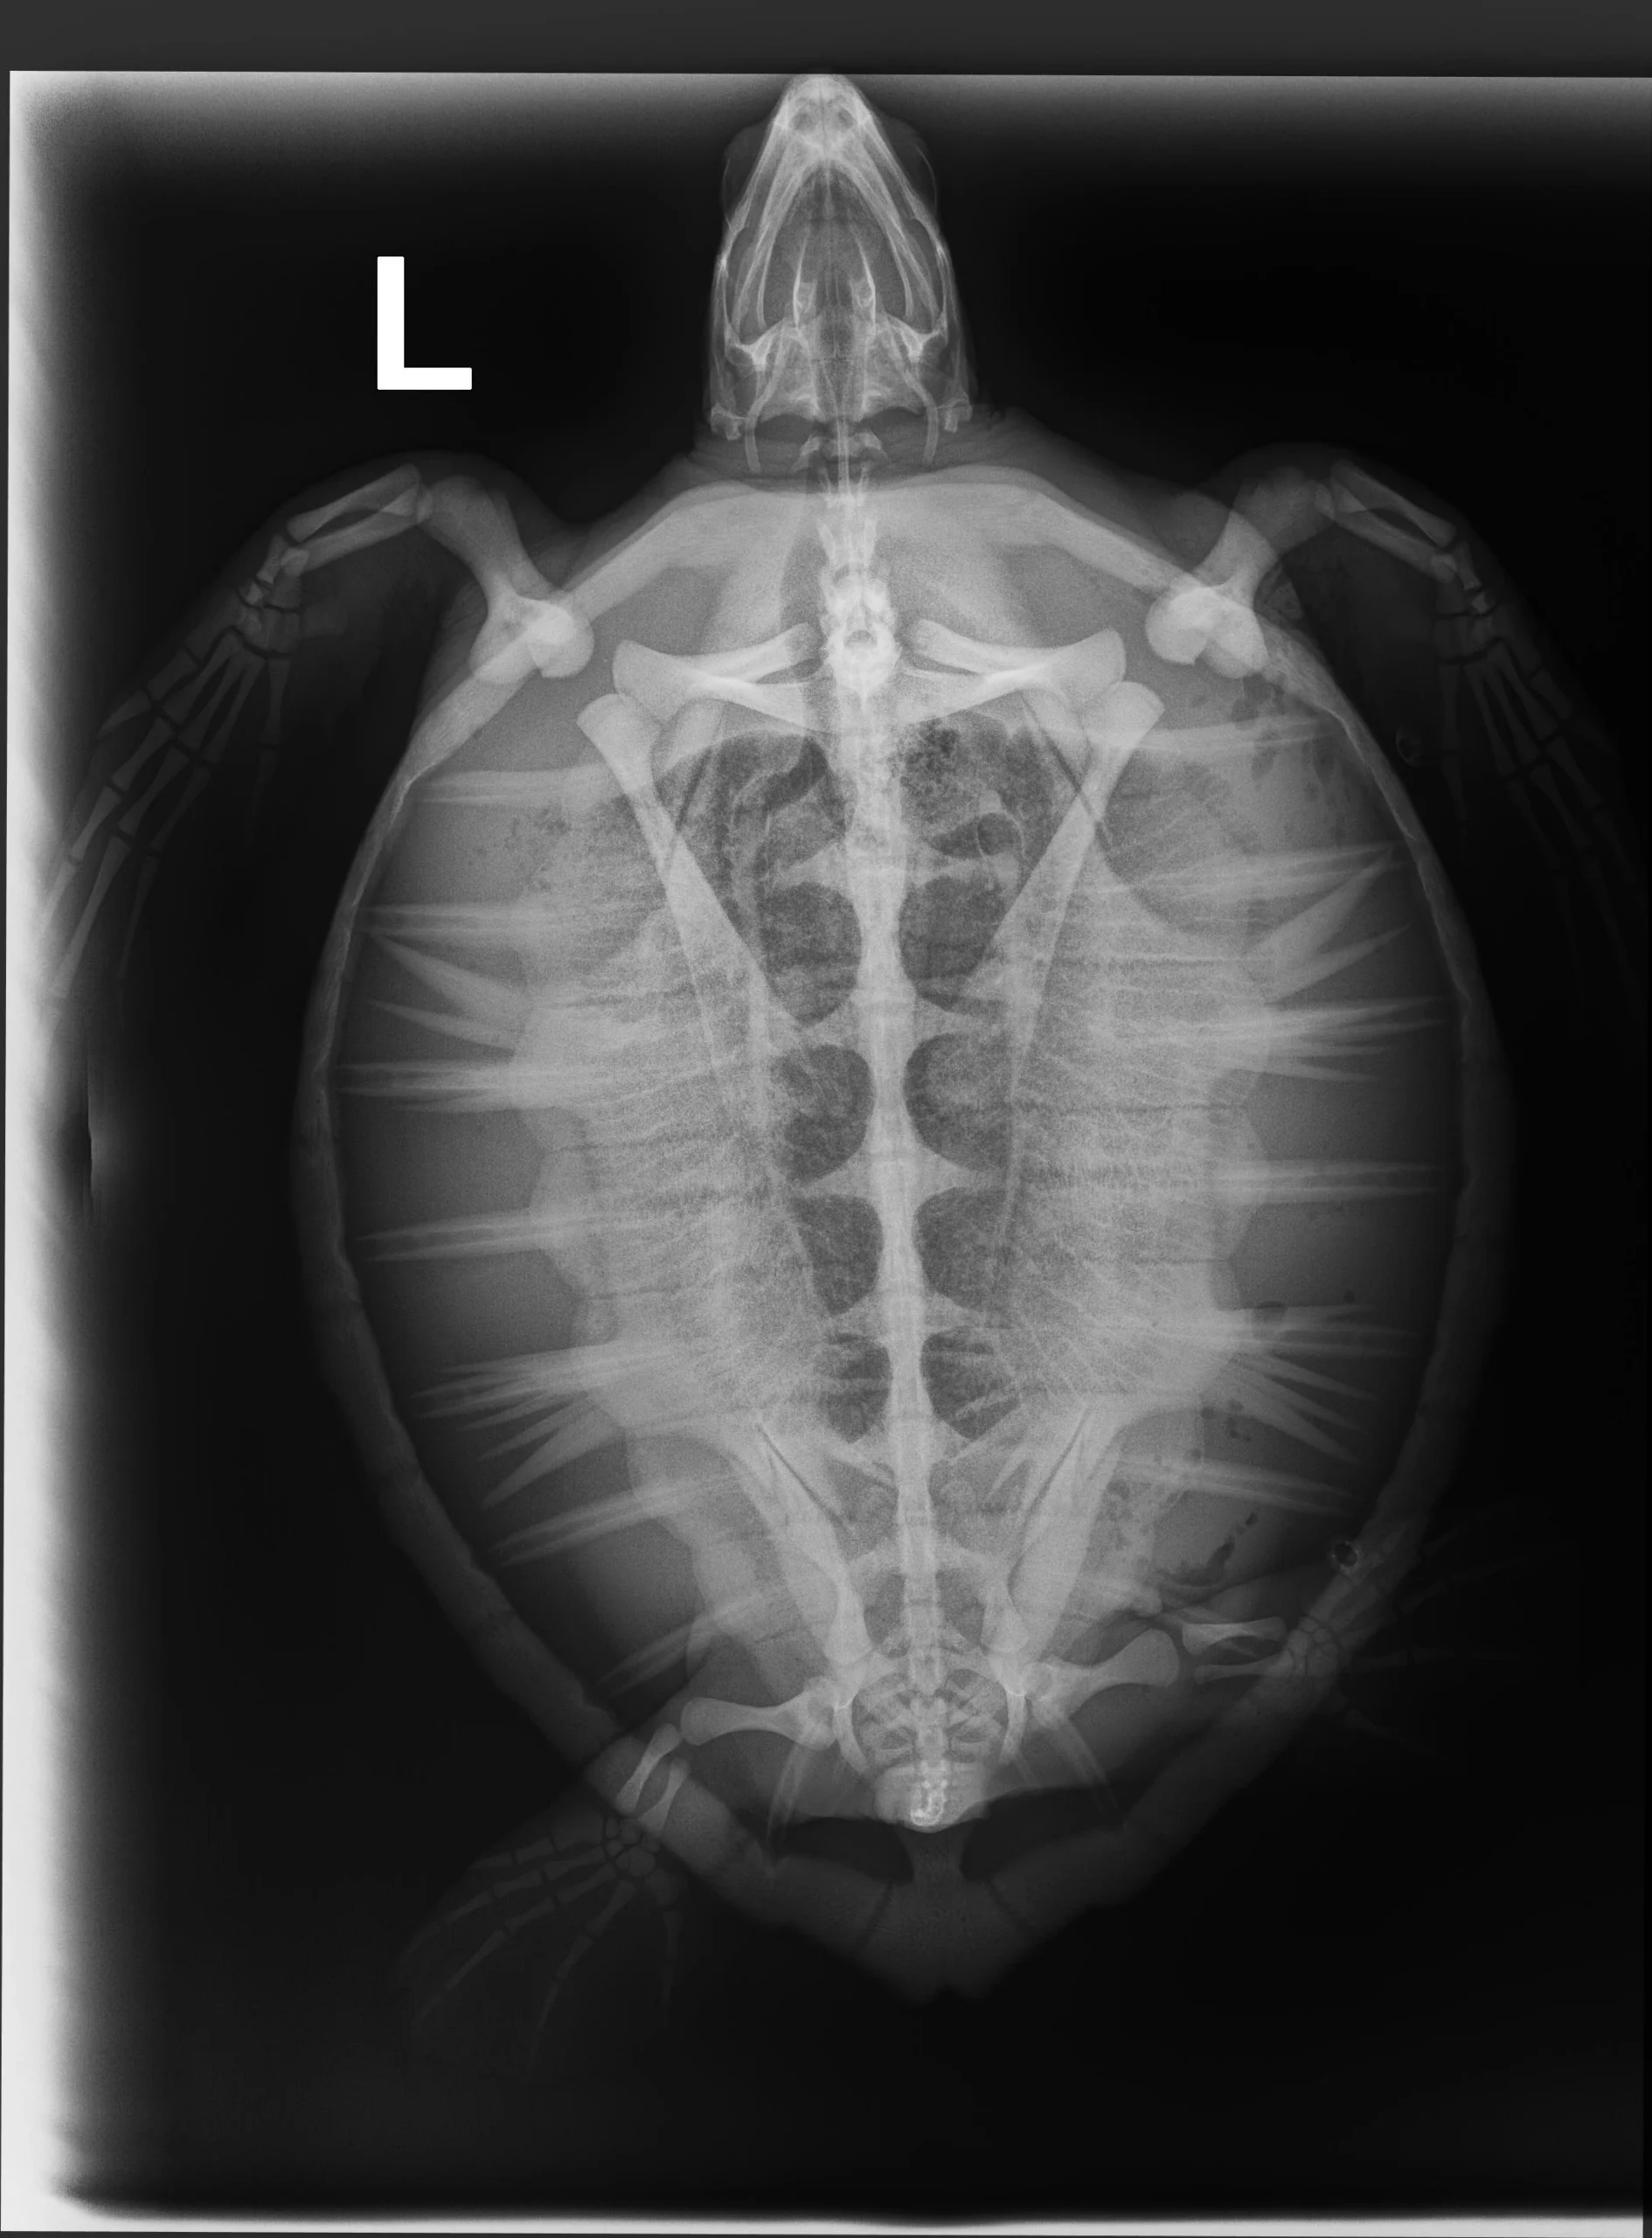

2.45 kg juvenile Atlantic Green sea turtle

External Carapace Notes: Very minor barnacles

Plastron: Minor scrapes

External Wounds: 2 small barnacles on carapace, one on plastron, light algae load on plastron

Hooked in the axilla (armpit) of the right front flipper